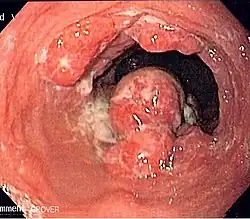

![]() | |

Endoscopic image of an esophageal adenocarcinoma | |

Although an occlusive tumor may be suspected on a barium swallow or barium meal, the diagnosis is best made with an examination using an endoscope. This involves the passing of a flexible tube with a light and camera down the esophagus and examining the wall, and is called an esophagogastroduodenoscopy. Biopsies taken of suspicious lesions are then examined histologically for signs of malignancy.